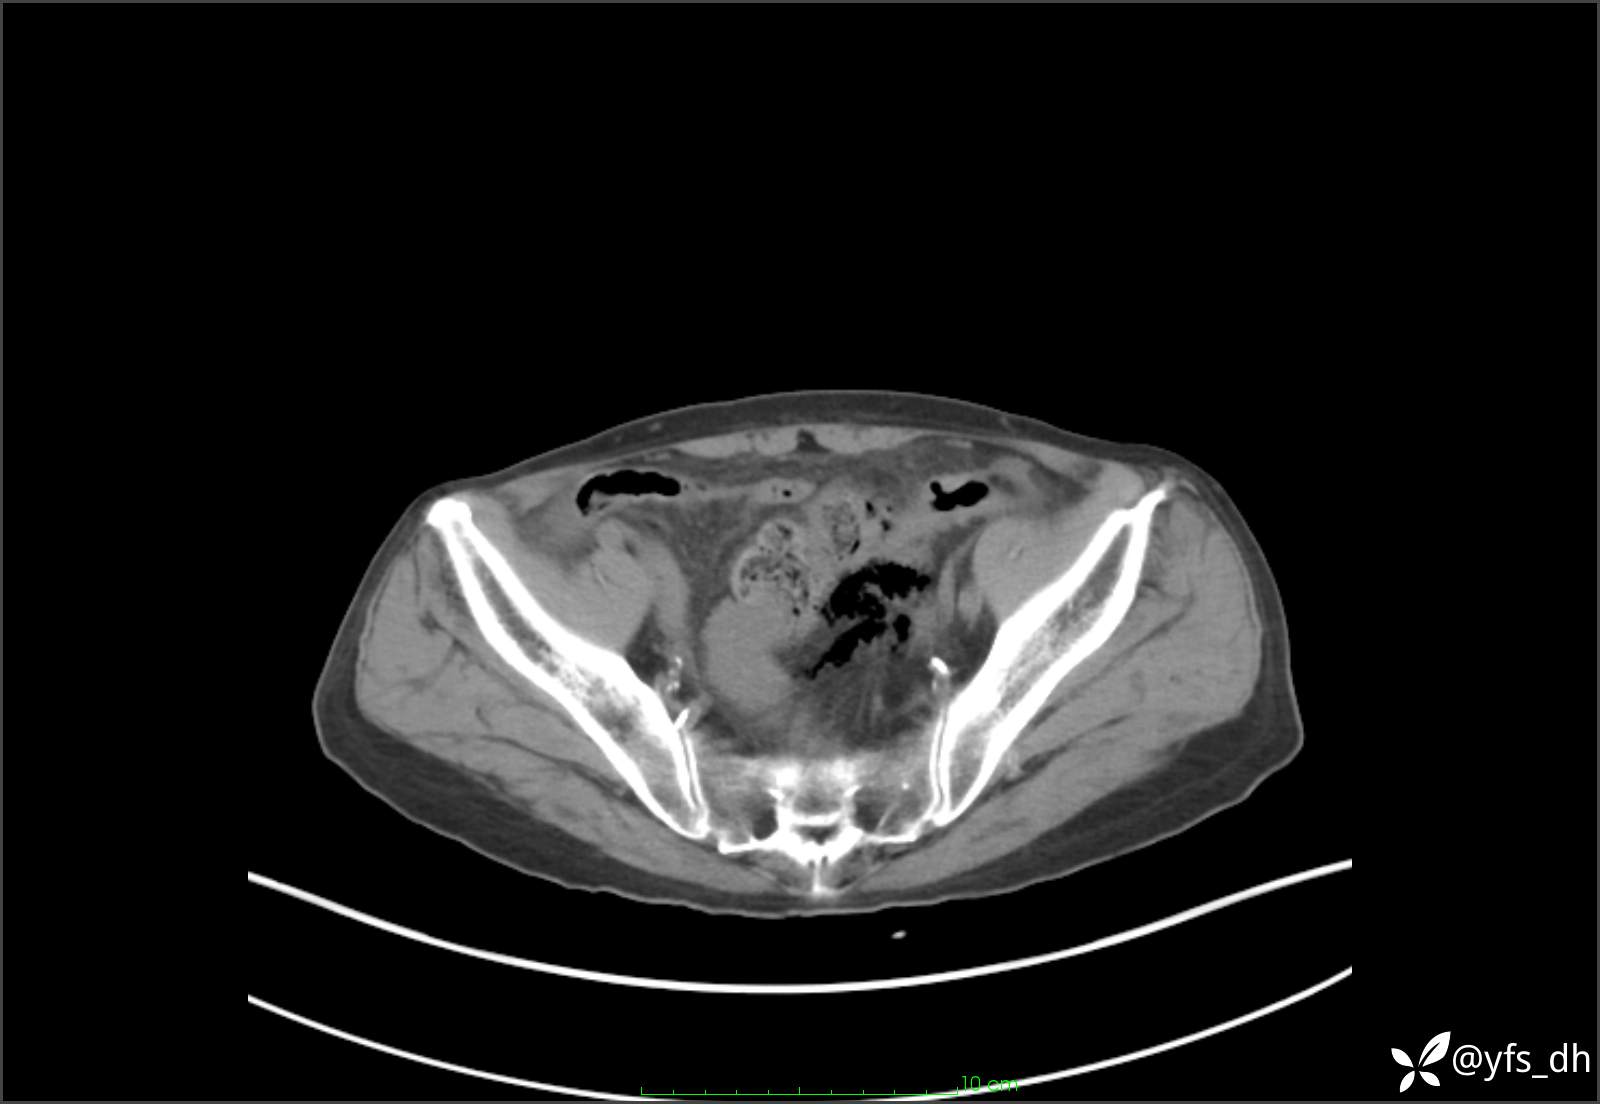

1.简要病史:患者4天前突发上腹部疼痛不适,但可以忍受。3小时前饭后突然加重,不能忍受后就诊。

2.简要手术记录:术中见腹盆腔大量肠液及粪便,乙状结肠中下段见一约3cm的破口。